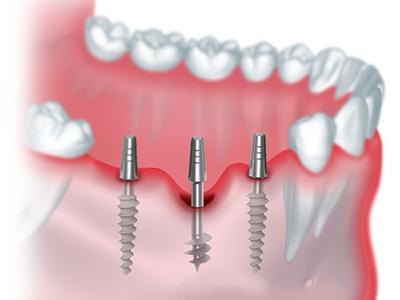

Elevate your dental care journey with our membership program, specifically designed for patients seeking teeth implants. As a member, you’ll benefit from reduced pricing on implant procedures, priority scheduling for consultations and treatments, and continuous follow-up care to ensure the best outcomes. Join today to access top-tier dental implant services and enhance your smile with confidence.